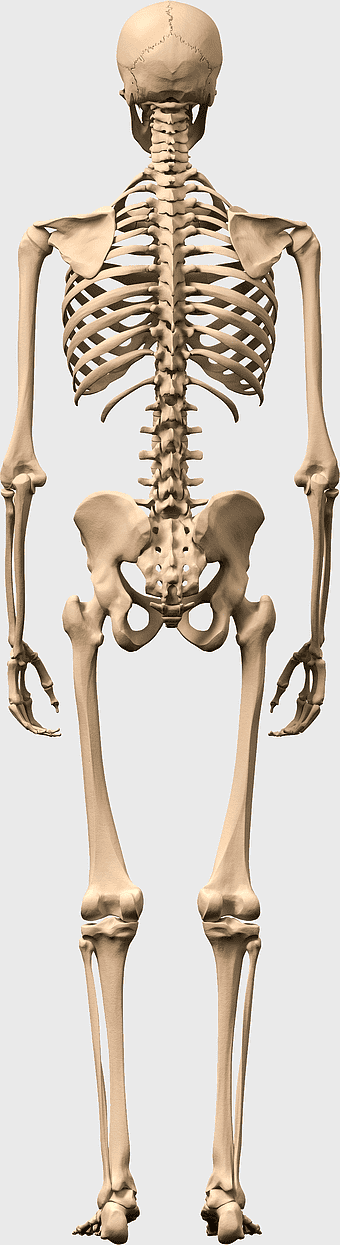

Human skeleton, human body anatomy, standing skeleton, bone structure, skeletal system, medical illustration, human anatomy study -

human skeleton illustration, white skeleton decor, rib cage anatomy, vertebral column drawing, skeletal system diagram, medical skeleton art, human bones structure -

Human skeleton, rib cage anatomy, upper limb bones, joints in human body, skeletal structure analysis, vertebral column details, anatomical illustration study -

human skeleton illustration, human anatomy bones, skeletal system diagram, human body structure, anatomical reference, medical illustration, educational skeleton image -